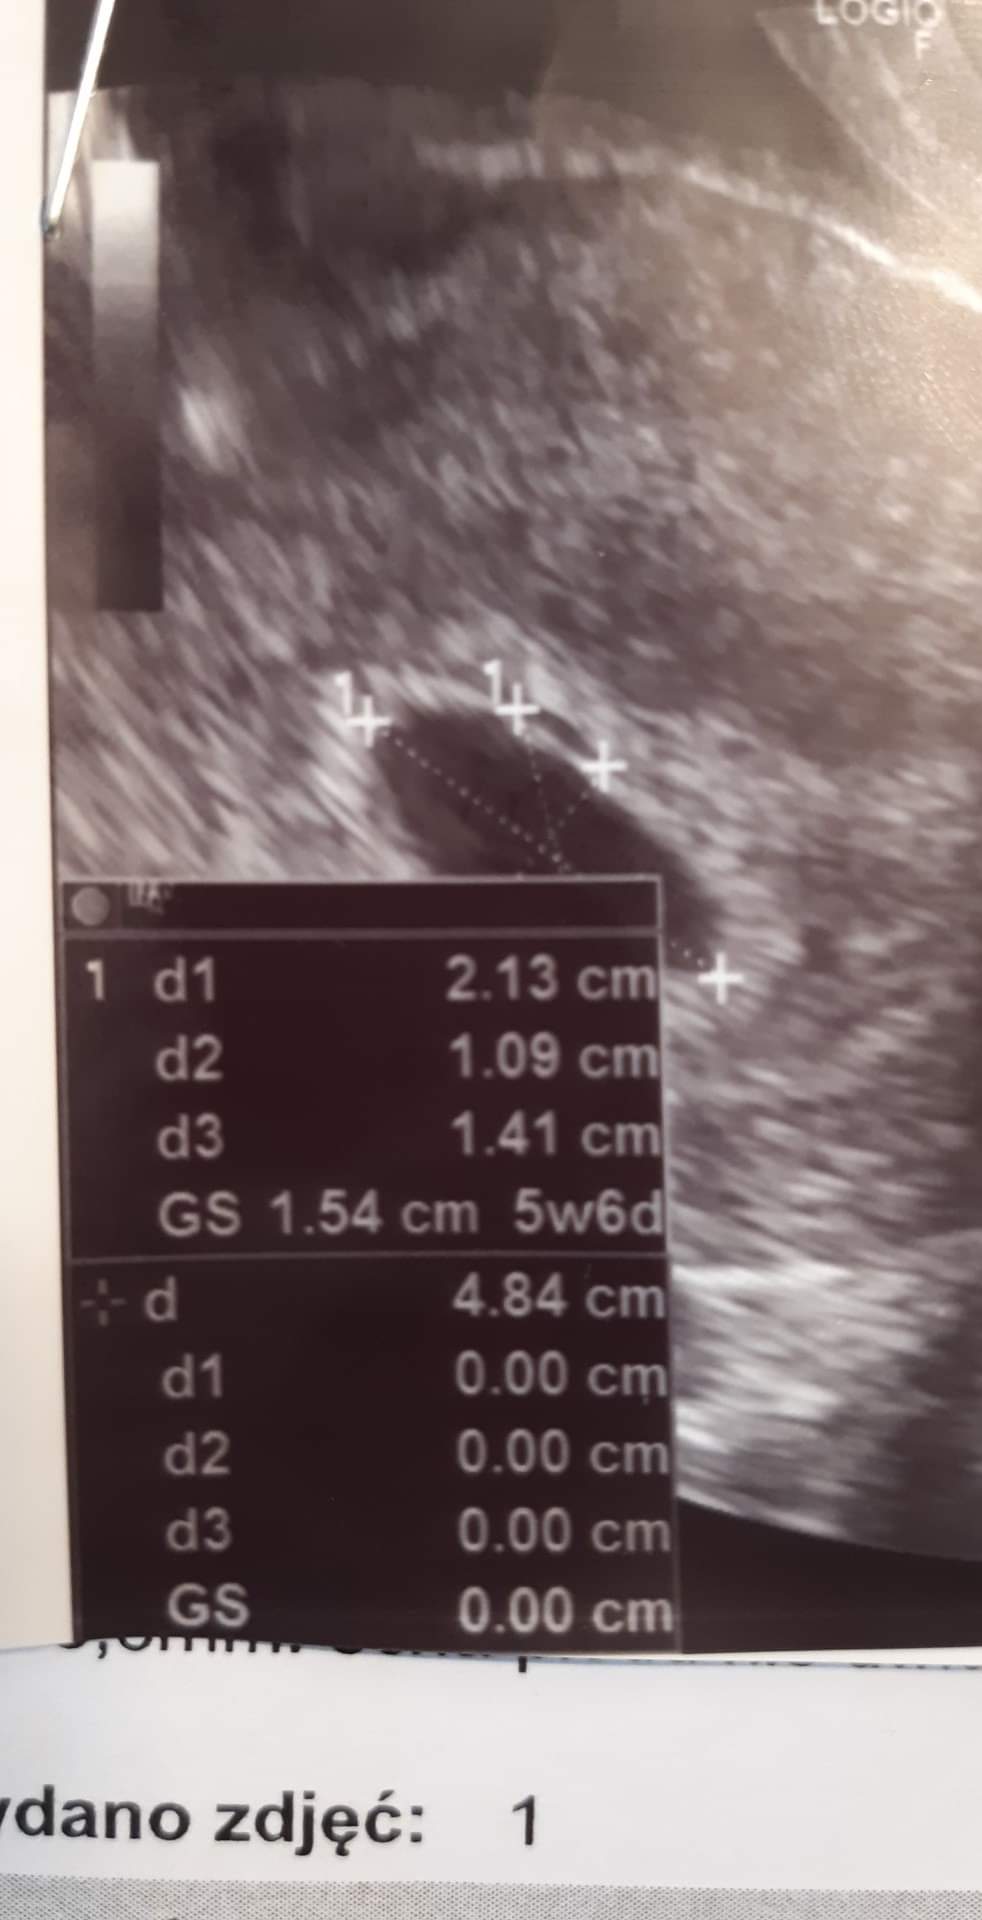

Z kalendarzyka 5tydzien 1dzienA w ktorym tc jestes?

Z wizyty u lekarza 4tydzien 1dzien

Od lekarza 4tydzien i 3dni. Pomyliłam sięZ kalendarzyka 5tydzien 1dzien